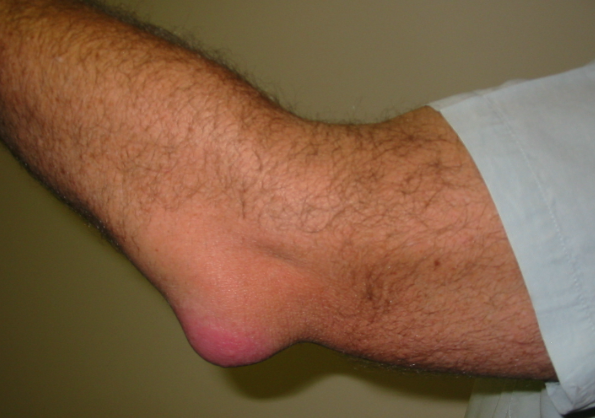

팔꿈치 점액낭염(주두 점액낭염)은 팔꿈치 뼈인 척골의 끝과 피부 사이에 위치한 점액낭(bursa)에 염증이 생기는 질환입니다. 이 점액낭은 관절을 보호하고 충격을 흡수하는 쿠션 역할을 합니다. 반복적인 압력이나 외상, 혹은 감염 등으로 인해 점액낭에 자극이 가해지면 염증이 발생해 증상이 나타납니다.

팔꿈치 부위의 통증과 붓기 (종창)

팔꿈치 피부가 붉어지고 따뜻해짐

만성화된 경우 팔꿈치에 물혹처럼 물렁거리는 덩어리가 만져짐

팔꿈치를 구부릴 때 통증이 심해지고, 운동 범위가 제한될 수 있음

눌렀을 때 압통(누르면 아픔)이 동반됨

심할 경우 고름이 차거나 열이 동반될 수 있음